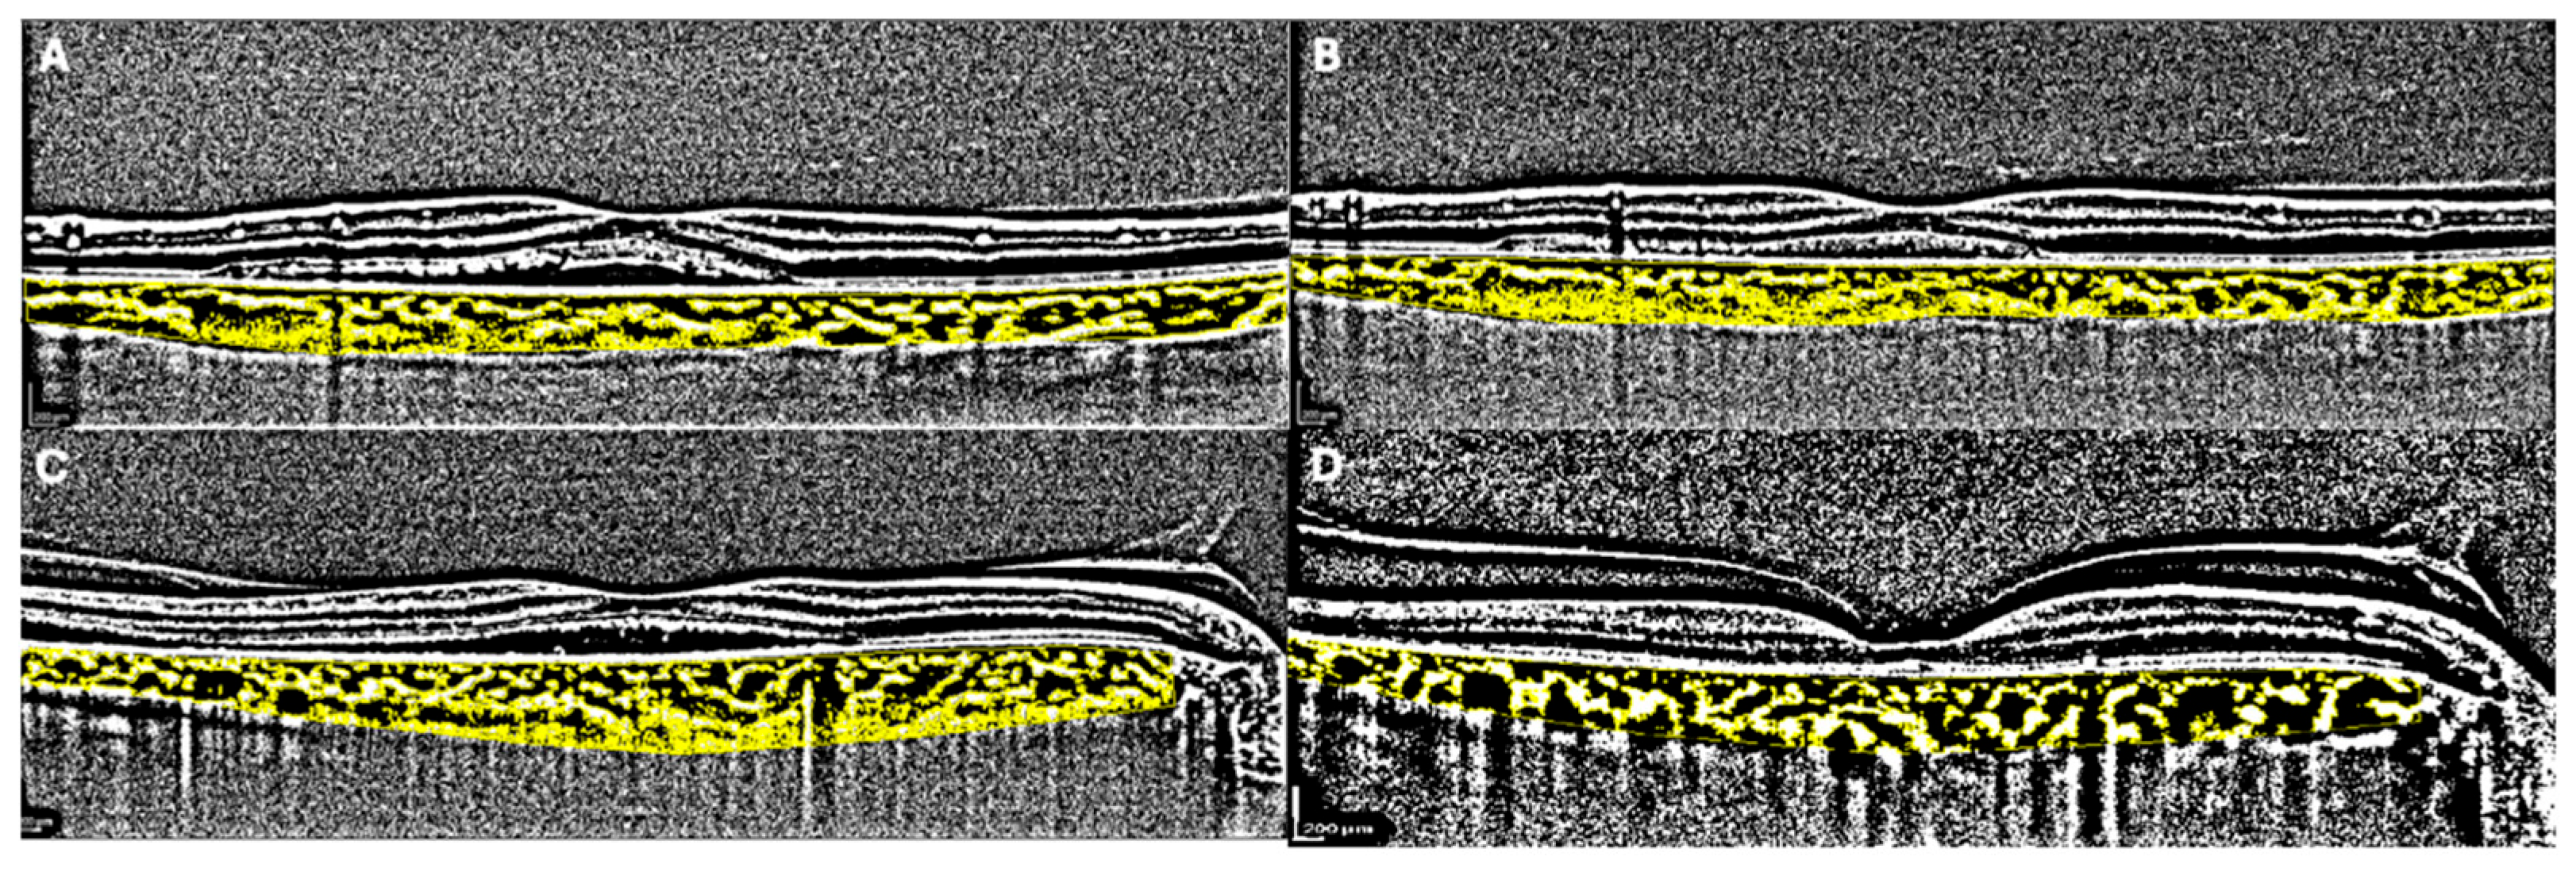

1. Introduction

2. Materials and Methods

2.1. SD-OCT Analysis

2.2. OCTa Analysis